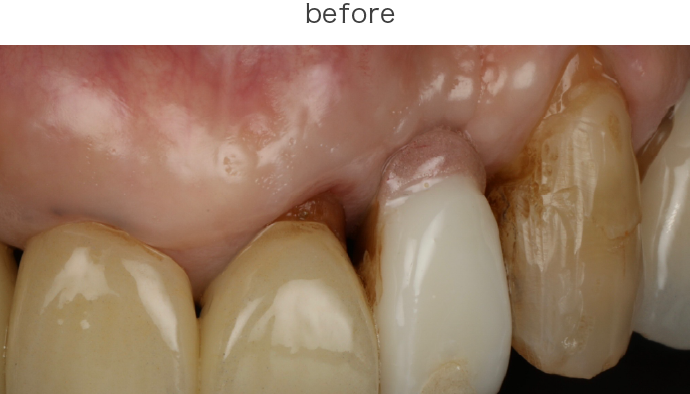

歯周病菌の炎症が歯茎の内側にも進行、歯を支える骨(歯槽骨)にも影響が出始めている段階。腫れ・出血・冷たいものがしみるなどの症状が出ることがあります。

歯槽骨の1/3〜1/2が破壊された状態。歯茎の腫れ・出血・膿・歯のぐらつき・口臭など自覚症状がかなり出ます。

| 治療内容 | 下段 歯周外科(再生療法) |

| 治療費 | 総額 88000円〜 |

| 治療回数 | 1回 |

| リスク | 術部の発赤、腫脹、疼痛、部分的なネクローシス |